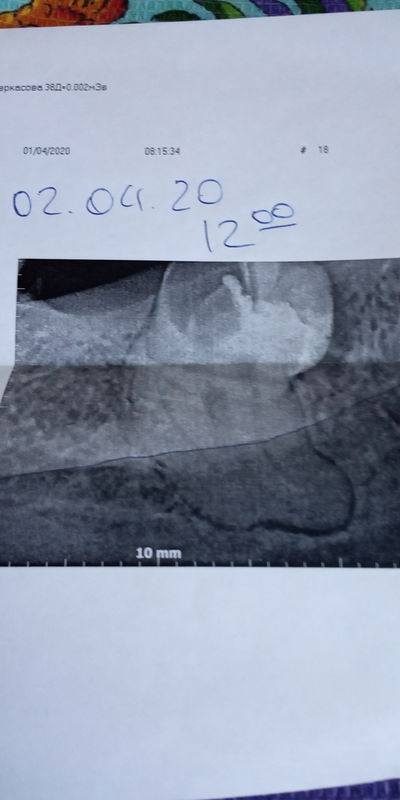

Посмотрите на снимки. Между верхним и нижним — разница в три недели. По ним хорошо заметно, что после удаления зачатков восьмёрок и «разблокировки», седьмые зубы сразу пошли в рост.